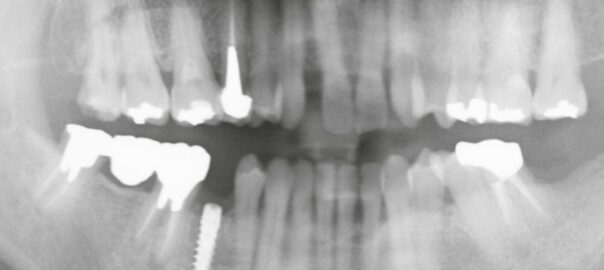

ブリッジからインプラントへの移行 ― 右下臼歯の症例

本日は「ブリッジが破折した後にインプラントで咬合を回復したケース」をご紹介します。 ご来院の経緯 患者様は右下の奥歯に痛みを感じて来院されました。 確認すると、右下に4本分のブリッジが装着されており、その一番奥の支えの歯 … 続きを読む ブリッジからインプラントへの移行 ― 右下臼歯の症例